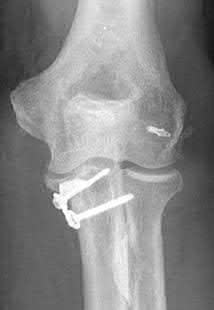

What physical exam finding is most likely to be found in association with the injury shown in Figures A and B?

The x-ray shows a fracture of the anteromedial facet of the coronoid with an intact radial head. Large anteromedial facet fractures are associated with varus posteromedial rotatory instability.

The anteromedial facet of the coronoid provides support to the medial elbow against varus stress. Varus and posteromedial force applied to the elbow results in disruption of the lateral collateral ligament (LCL) from its proximal origin. The coronoid is fractured as it is forced against the medial trochlea.

Coronoid fractures of significant size involving the sublime tubercle (insertion of medial collateral ligament) result in varus instability.

Steinmann reviews the anatomy, diagnosis, classification and treatment of coronoid fractures with a focus on surgical exposures and fixation techniques. He states that when a coronoid fracture is associated with a pattern of varus instability, it requires fixation with either suture, buttress plating or screw fixation. Concomitant LCL repair or reconstruction will also be necessary.

Doornberg et al. reviewed 67 coronoid fractures to determine whether type of coronoid fracture correlated with pattern of instability. They found strong

associations between (1) large coronoid fractures and trans-olecranon fracture-dislocations, (2) small fractures and terrible-triad injuries, and (3) anteromedial facet fractures and varus posteromedial rotational injury mechanisms.

Doornberg et al. evaluated 18 patients with a fracture of the anteromedial facet of the coronoid. They found that malalignment of the anteromedial facet fragment was associated with arthrosis and a fair or poor result.

Figure A is an AP view of an elbow with an anteromedial facet of the coronoid fractured. The lateral joint space is widened due to injury to the LCL. The medial joint space is narrowed and collapsed. A lateral view is shown in Figure

B. Illustrations A and B show AP and lateral views of a coronoid fracture fixed with buttress plating. The LCL origin was fixed with a suture anchor. Illustration C shows the O'Driscoll classification of coronoid fractures. Illustration D lists injury patterns that suggest posteromedial versus posterolateral rotatory instability.